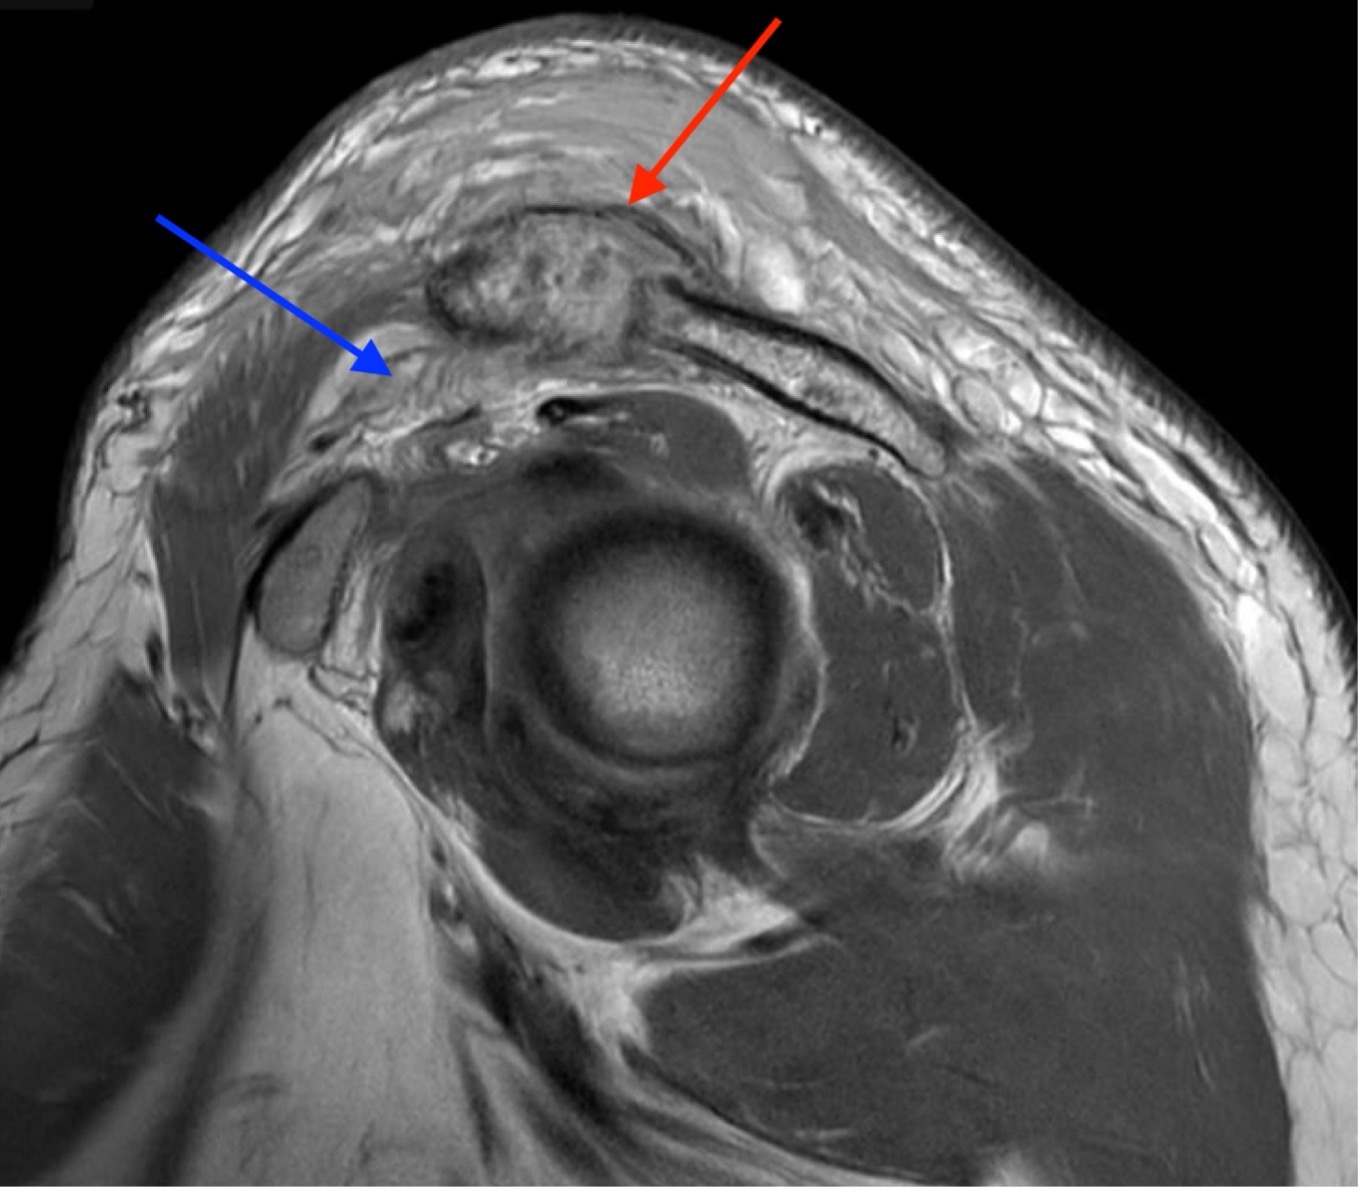

Septic arthritis of native joints is uncommon, but the condition can be threatening to life and limb if left untreated.1 Septic arthritis of the acromioclavicular (AC) joint of the shoulder is particularly rare and has only appeared sparsely in medical literature, mainly through individual case reports. Early recognition and treatment of the condition is vital, but diagnosis of septic AC arthritis can be difficult due to its presentation with vague symptoms and nonspecific laboratory findings. This case report describes the care of a patient with poorly managed diabetes who presented to the emergency department with one month of pain and swelling of the left shoulder and two weeks of pain and swelling in the right ankle. Imaging revealed fluid in the AC joint, and laboratory evaluation showed an elevation in inflammatory markers, including leukocyte count, C-reactive protein (CRP), and erythrocyte sedimentation rate (ESR). The patient's hospital course was complicated by methicillin-sensitive Staphylococcus Aureus bacteremia without evidence of sepsis. The patient underwent open debridement and washout of both the ankle and AC joint without complication. After recovery, the patient was discharged to a rehabilitative center with IV antibiotics and weekly follow up care with infectious disease specialists. This case illustrates the importance of early diagnosis and treatment of septic arthritis, even in less common joint spaces, to prevent progression of this dangerous disease.